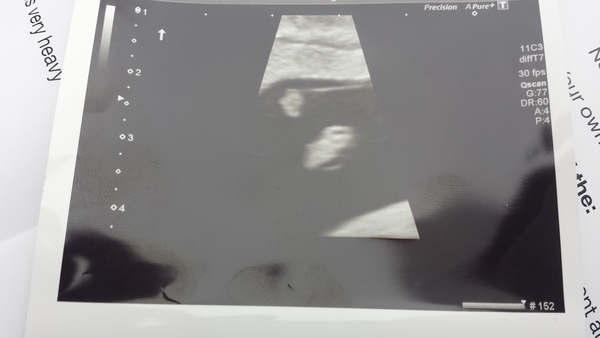

ImGonnaSingTheDoomSongNow · 18/02/2017 08:29

I don't know for sure but I would imagine that sounds about right. I've added a (rather crappy) picture of what was seen on my internal scan at 7+1, which as you can see is not much. The small blob at the top is the yolk sac and the bigger blob is the embryo.

I hope that helps somewhat.

Thanks Imgonnasing I reckon I'm about 2 weeks earlier than your scan pic at 7+1 so hopefully this will be what we see when we go back again in 2 weeks time